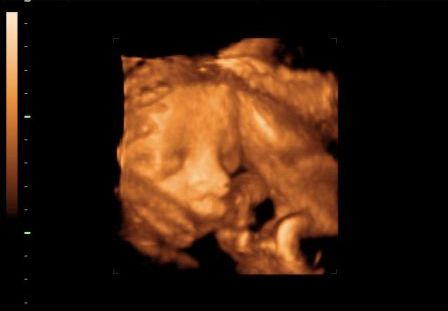

Kép

Barni 30hetesen

(Nem nagy rajongója az uh-nak, ez a legtöbbet mutató kép róla...)